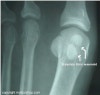

X-ray : 종자골 골절(Sesamoid fracture, Sesamoiditis)

AP view, lateral view, axial view 촬영을 시행합니다(가쪽 종자뼈는 oblique view에서 가장 잘 보입니다).

이분 종자뼈(bipartite sesamoid)가 정상이 변이형으로 존재하므로 골절과 감별해야 합니다.

정상적으로 25%에서는 선천적으로 종자뼈가 2분 혹은 여러 개로 갈라져 생기며, 이때는 불규칙한 경계를 보이는 골절과 달리 X-ray상 경계부가 부드럽습니다.